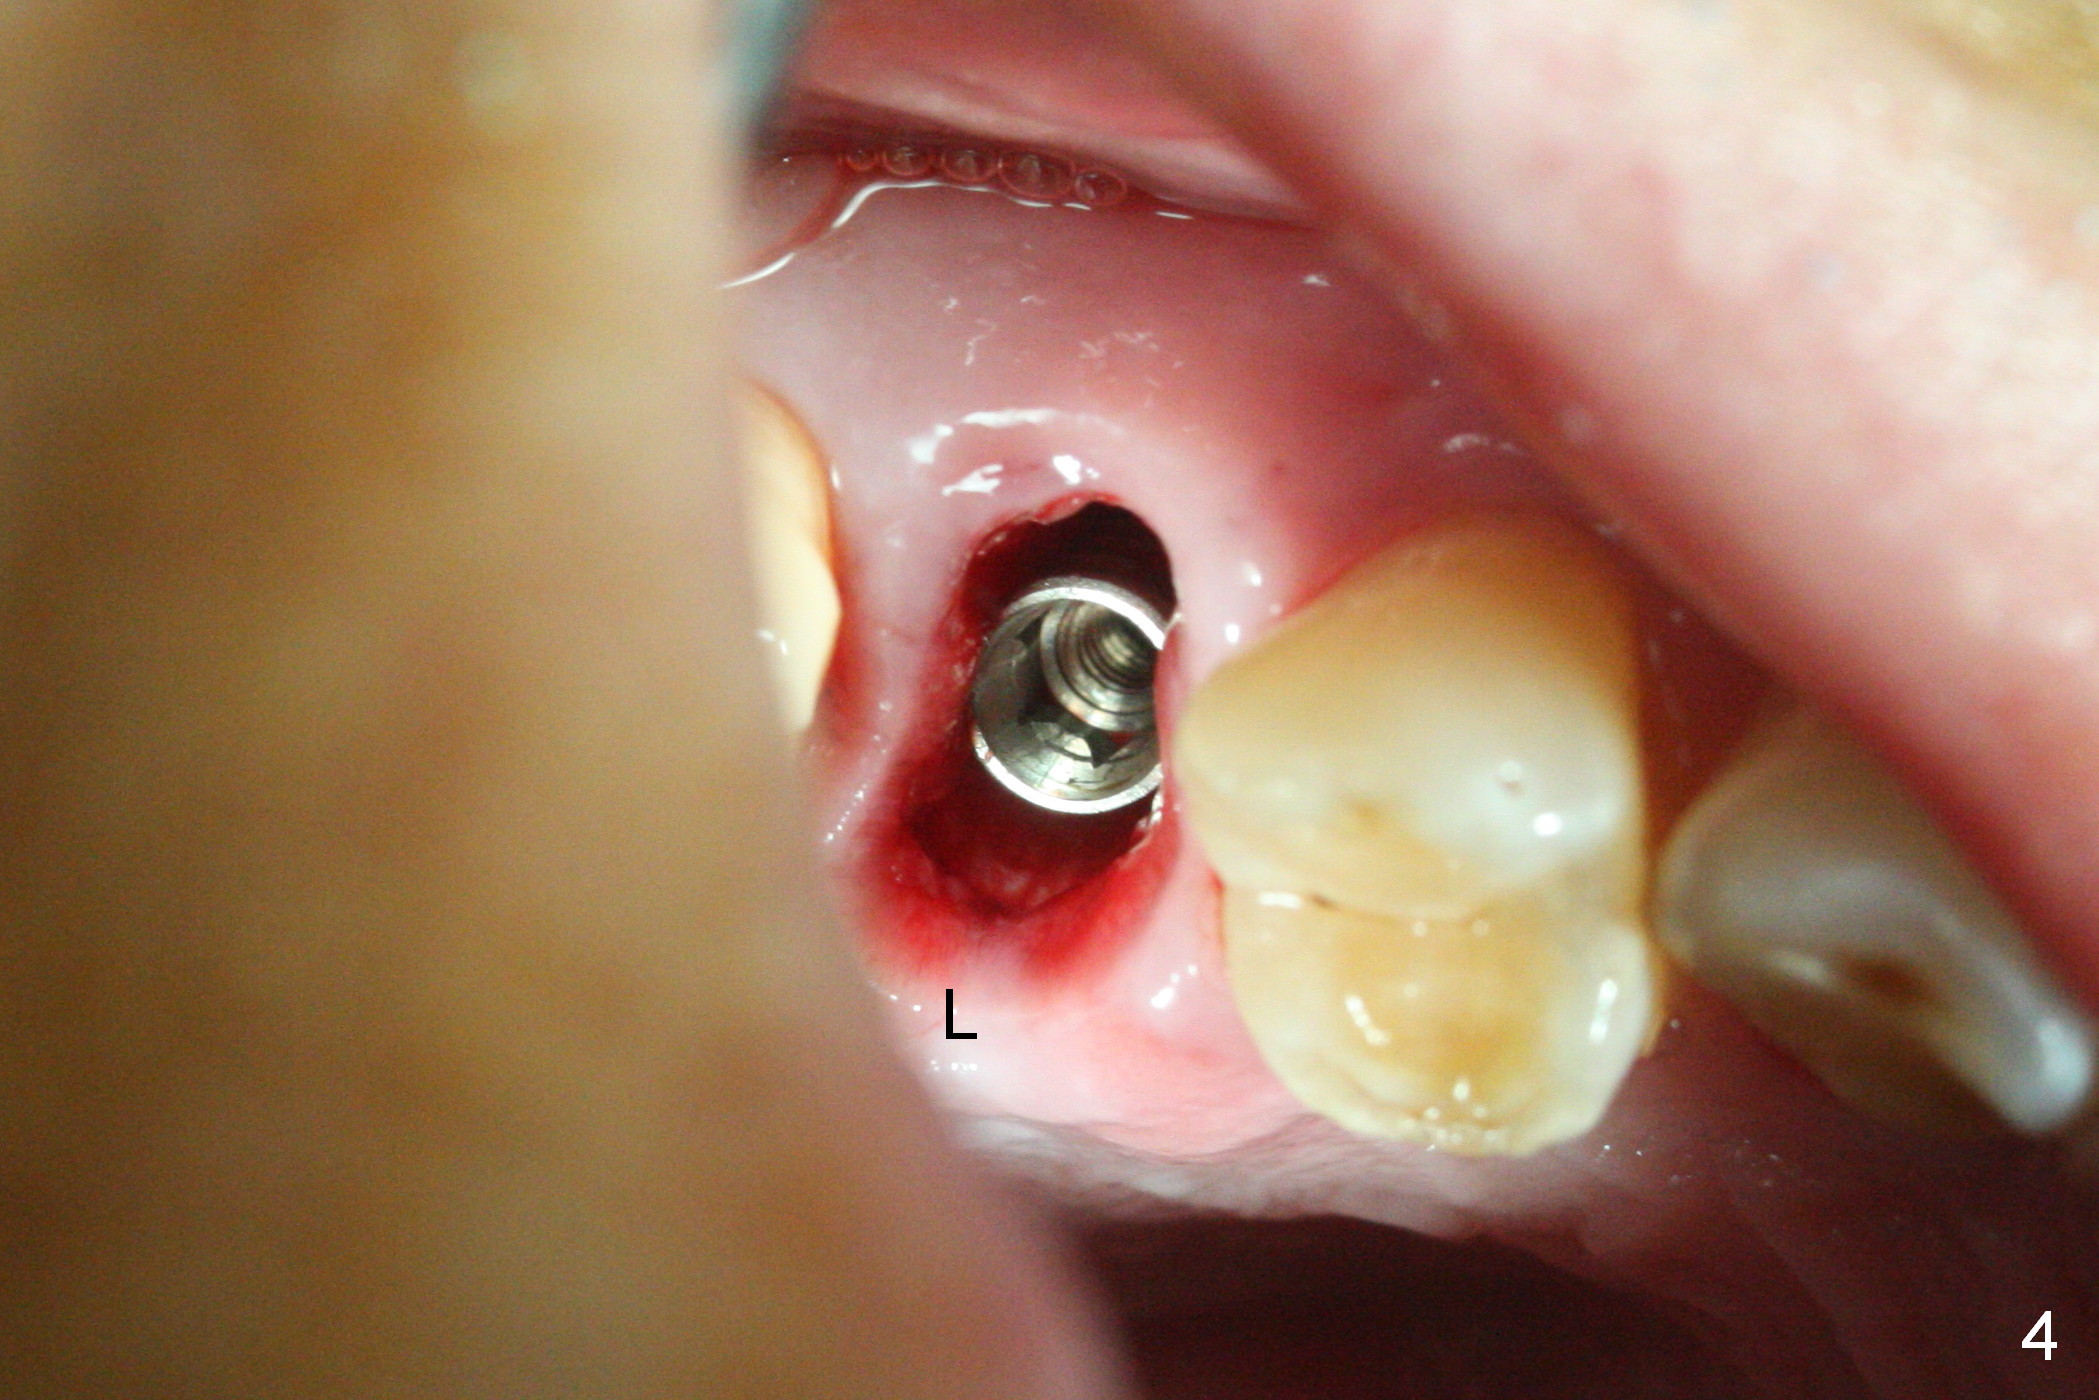

A 47-year-old man returns emergently with subgingival fracture of the lingual (L) cusp of the tooth #4 (Fig.1-3).  After extraction (no bony defect) without drilling, a 4x11 mm dummy implant is placed as a tap drill with satisfactory stability (Fig.4,5).  To get subcrestal placement, a shorter (4x9 mm) implant is inserted with insertion torque of < 35 Ncm.  In retrospect, a larger implant (4.5 mm) would be better in term of primary stability.  After allograft placement into the buccal and lingual gaps, a 4.5x4(4) mm abutment is placed for an immediate provisional.  There is a peri-implant gap 7 months postop (Fig.7<, as compared to the implant at #2 (6 months postop)) .  When the loose abutment is being retightened, the patient feels pain, although the gingiva appears healthy (Fig.8).  A larger implant should have been used; the abutment should have been removed.  The implant dislodges while the abutment is untightened 8 months postop.  The osteotomy is found intact.  A 4.5x11 mm dummy implant is placed 2 mm subgingival with 20 Ncm (Fig.9).  When a 4.5x11 mm definitive implant is placed 3 mm subgingival (Fig.10,11), torque reaches 50 Ncm.  A 5.5x3 mm healing abutment is placed.  Three months postop, the implant is stable (Fig.12,13) and impression is taken.